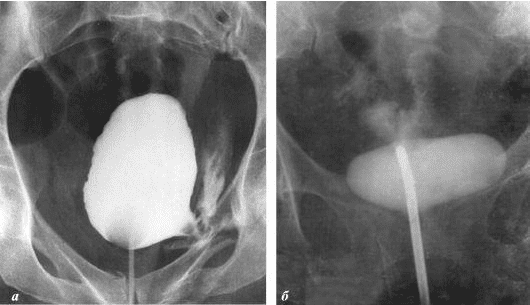

Želim da vam pokažem neke fotografije tako da sami možete da vidite šta se dešava urogenitalnom sistemu i drugim organima muškarca koji nema seksualne odnose.

Evo kako izgleda upala prostate uzrokovana stagnacijom sperme (kada se testisi ne prazne). Trajna upala dovodi do adenoma prostate, a kasnije do raka prostate (prema statistikama, 38% muškaraca umire zbog ovoga). Zbog odsustva seksa, ovo se dešava uvijek i to je razlog zašto se adenom prostate naziva "bolešću starih".